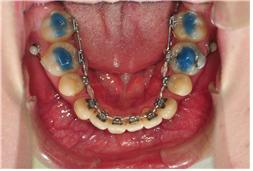

그래서 이번 월치료에는 하악와이어교체해주시고~ 고무줄들을 새 것들로 교체해주셨어요~

앞니가 올리는 마무리단계라 그런지 선생님께서 이번 에는 4주후가 아닌 6주후

방문하라고 하시구요~